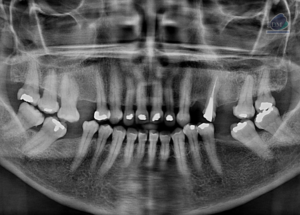

Paciente femenina de 78 años, es referido al Instituto de Diagnóstico Maxilofacial – IDM (Sede Surco) para evaluación de áreas óseas y planificación de implantes